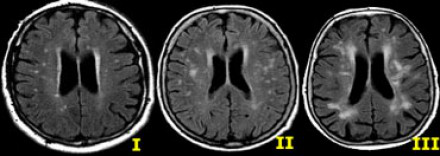

多發(fā)性增強病灶的鑒別診斷

圖片二

在上圖中,是各種多發(fā)性增強白質(zhì)病灶圖像,我們對其中部分病例進行詳細討論。需要說明的是,以下鑒別診斷中提到的疾病與上圖中的圖像并不完全重合。

血管炎

大多數(shù)血管炎性疾病的MRI成像特點是點狀增強。

腦部血管炎常見于系統(tǒng)性紅斑狼瘡、結(jié)節(jié)性多動脈炎(PAN)、白塞病(Behcet)、梅毒、韋格納肉芽腫(Wegener)、干燥綜合征(Sjogren)和原發(fā)性中樞神經(jīng)系統(tǒng)血管炎。

白塞病(Behcet)

白塞病更常見于土耳其患者。典型MRI表現(xiàn)是急性期出現(xiàn)腦干病灶結(jié)節(jié)性增強。

其他疾病的腦轉(zhuǎn)移病灶

其他疾病的腦轉(zhuǎn)移病灶周圍常包裹有水腫帶。

交界區(qū)腦梗死

周圍交界區(qū)腦梗死在病變早期可出現(xiàn)增強病灶。